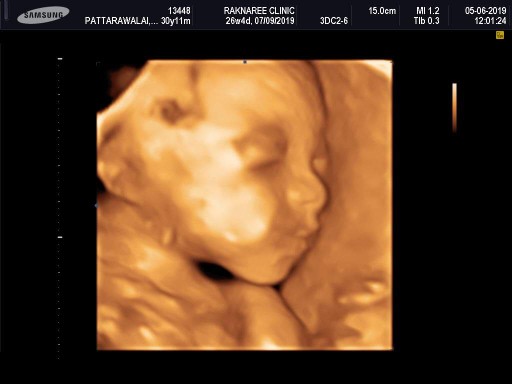

ของเราซาวด์ตอน 28วีค4วันค่ะรู้เพศชัวร์ๆตอน 21วีค คุณหมอแนะนำให้ซาวด์ 4 มิติช่วง 25วีค ขึ้นไปจะคุ้มและเห็นชัดเจนกว่าจ้า

26 weeks ผู้หญิง น้องแอลลี่ ลูกครึ่งเกาหลีจ้ะ